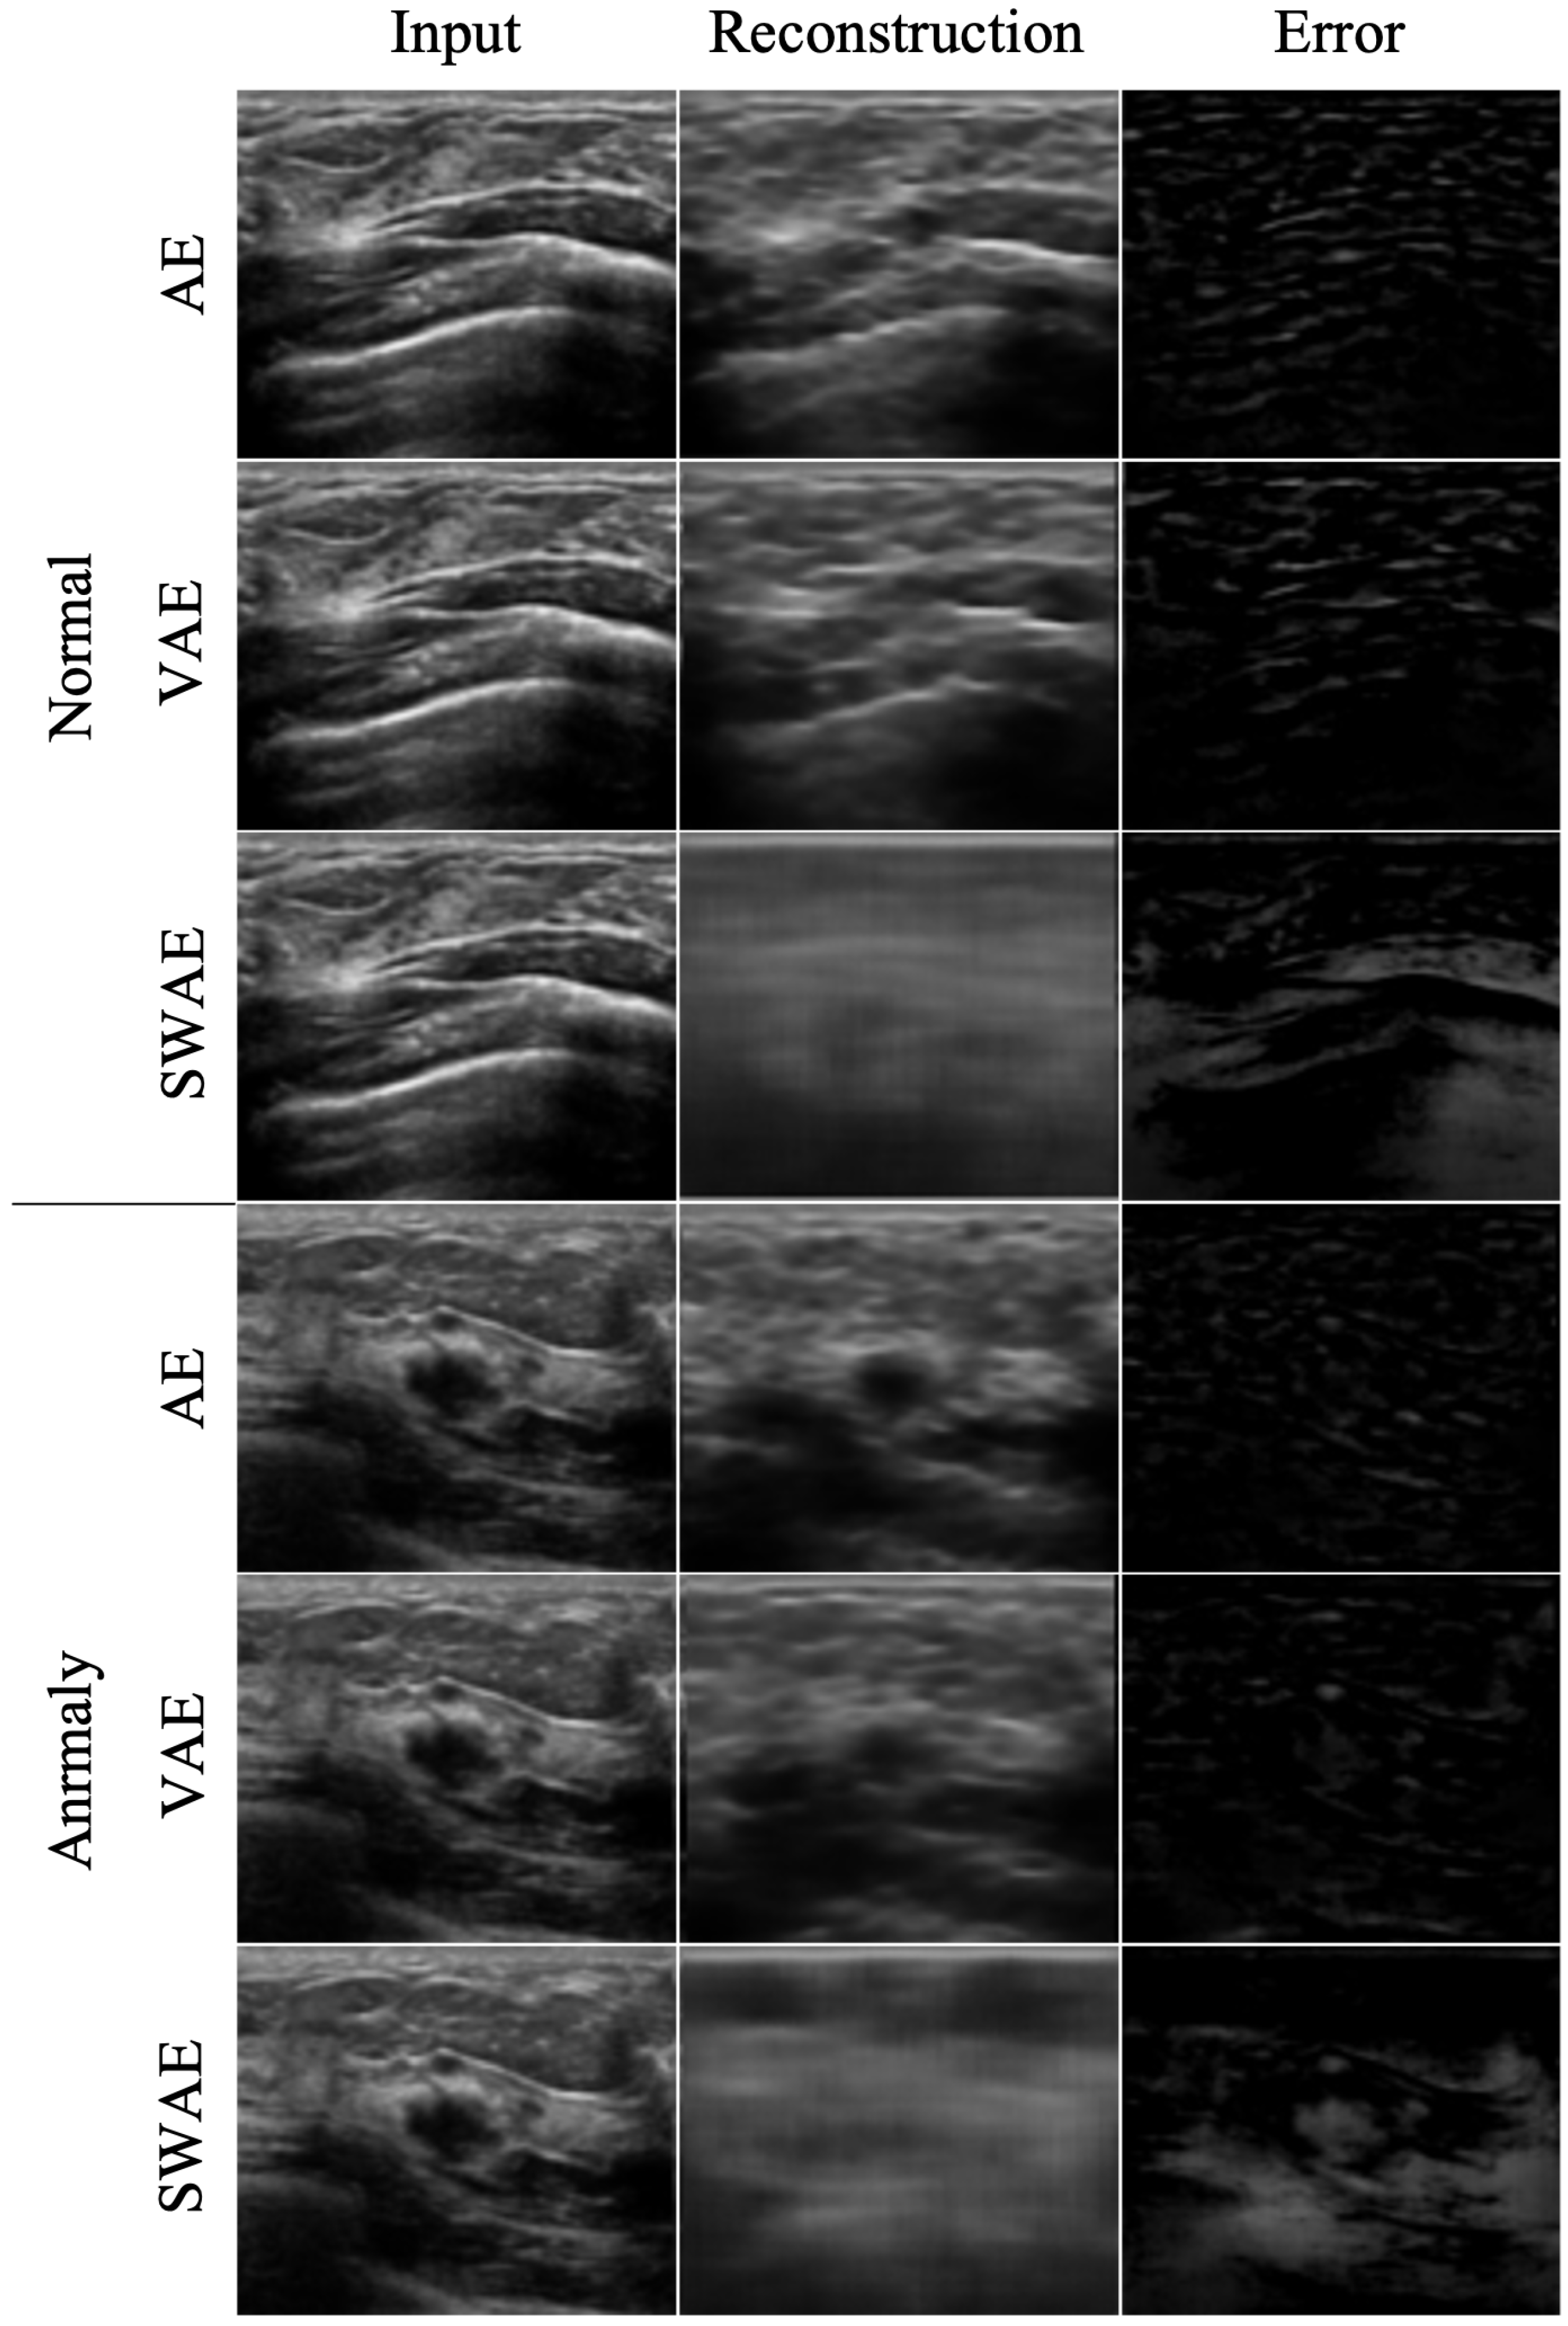

The reconstruction performances of the models are presented in Table 4 by comparing the average RMSE of the verification process using normal ultrasound images and the average RMSE of abnormal ultrasound images. In the image reconstruction process by an AE, the smaller the RMSE value, the better the reconstruction performance. However, in a test process for abnormal ultrasonic images, a larger RMSE value indicates that the input image is not well-reconstructed. This means that the input image contains abnormal features that are difficult to reconstruct by the model. The pixel-wise differences between the input and reconstructed images would be suitable for identifying an anomalous region. In the comparison experiment for the three models, the RMSE value increases in the order of SWAE, VAE, and AE, and the anomalous region detection performance is found to be the best in the SWAE model. Examples of the image reconstruction results for each model are shown in Figure 9 below.

Figure 9.

Reconstructed images by model.

We confirmed that the AE model with the smallest RMSE value yielded restoration as the input. For the VAE model, although the normalization value was considered in learning, the results were similar to those of the AE model. This shows that it is difficult to find an anomalous region in an error image by restoring the anomalous region similar to the input as a result of the test by inputting an abnormal image. Conversely, the reconstructed images of the SWAE model, which showed the highest RMSE value in the evaluation process, did not restore abnormal features. The anomalous region could be verified in the different maps more accurately.